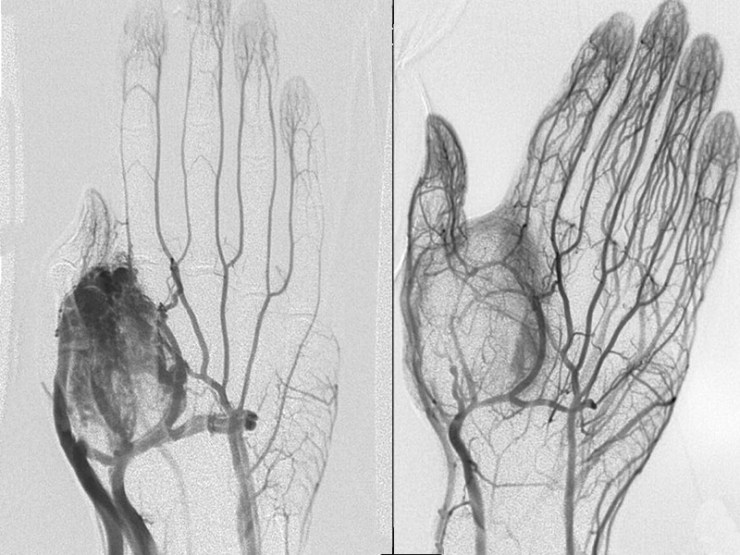

Absolute ethanol embolization is the only effective solution to destroy nidus.

Absolute ethanol if injected into nidus directly it will destroy inner lining cells of the nidus and nidus will resolve by it.

Absolute ethanol goes into systemic circulation and it will destroy normal vessels also. And also leads to other fatal complications. So one has to go to centre where they are treating such cases with absolute ethanol and enough experience of it. Bankers Vascular Centre is one of the pioneer in India to start absolute ethanol embolization technique & has lot of experience to treat with absolute ethanol embolization.

Case 1: Venous malformation of chest wall, suffering from many years. With our treatment pt’s pain disappeared within 3rd sitting.